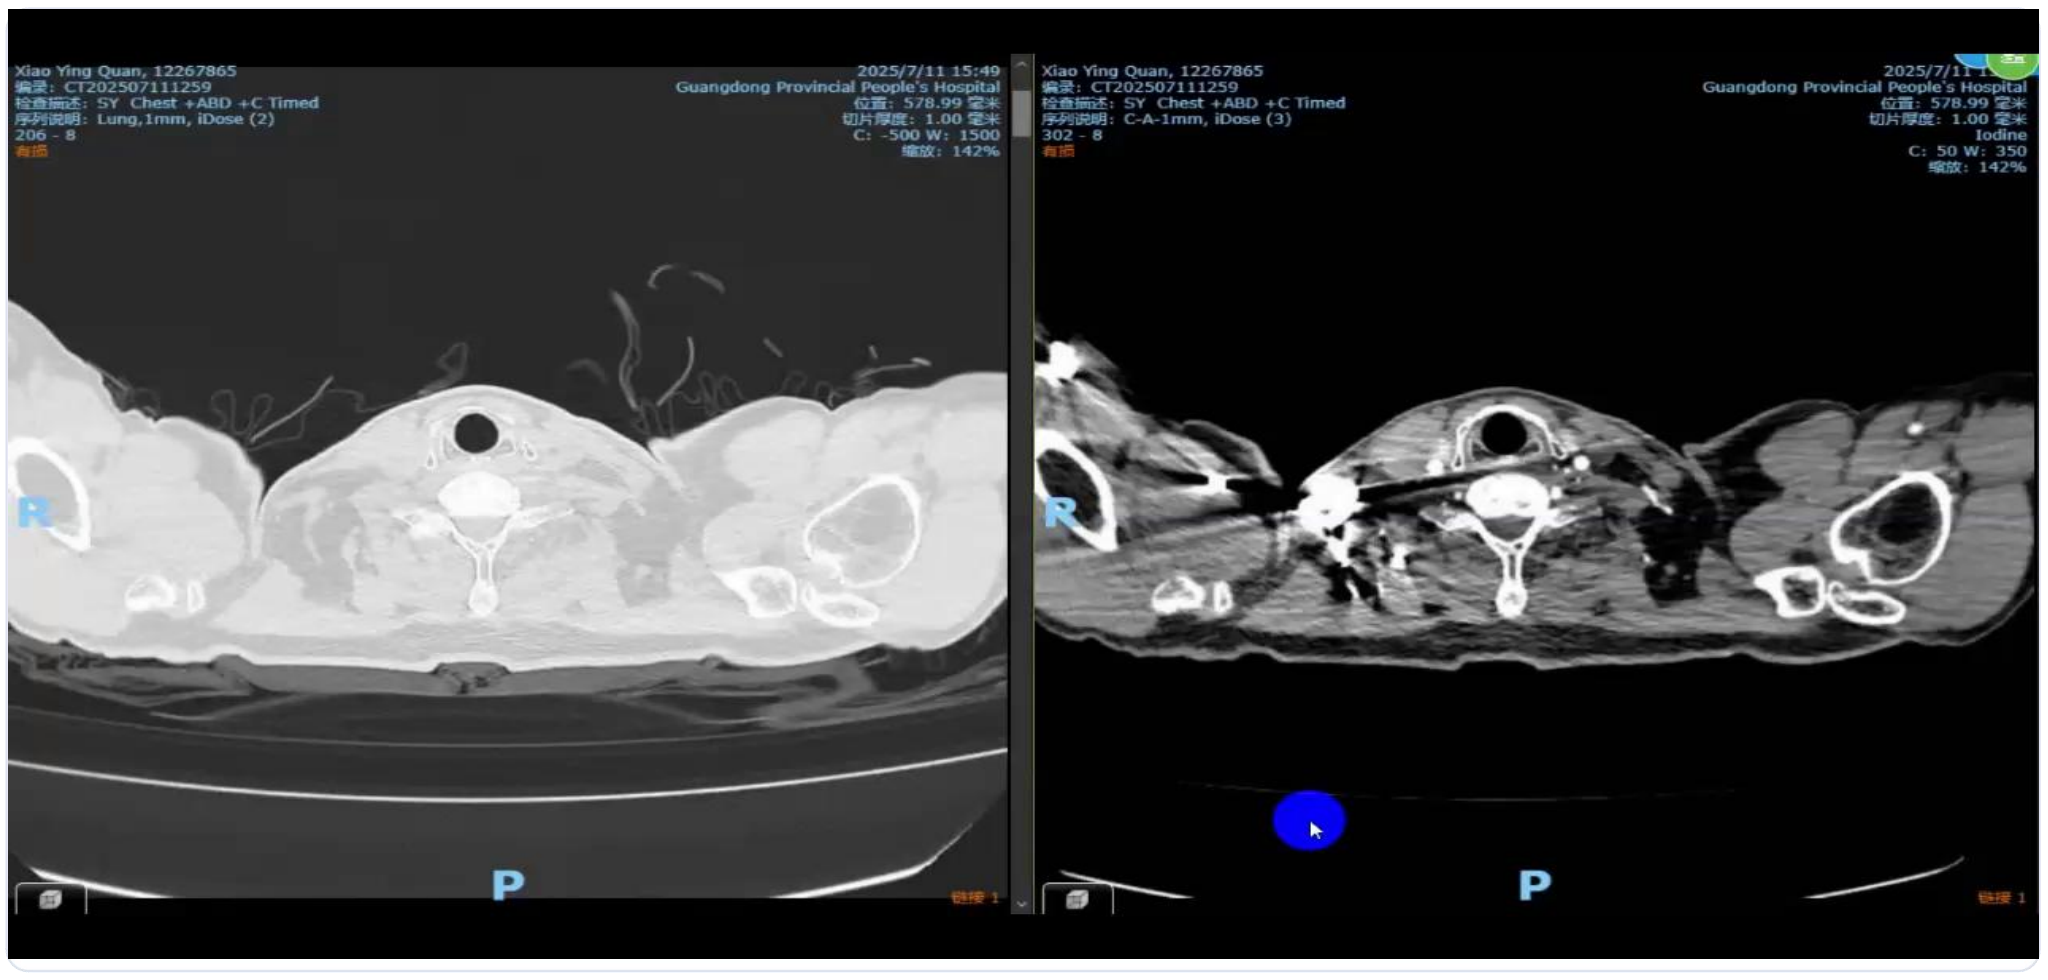

2022.12.4 疗效评估:PET/CT显示原发灶尺寸缩小(8.1×5.6 cm → 4.2×2.8 cm);SUVmax显著下降(21.8 → 5.3);多个淋巴结代谢活性明显降低

截至2025年7月,无事件生存期(EFS)超过34.2个月,影像学检查无复发迹象。